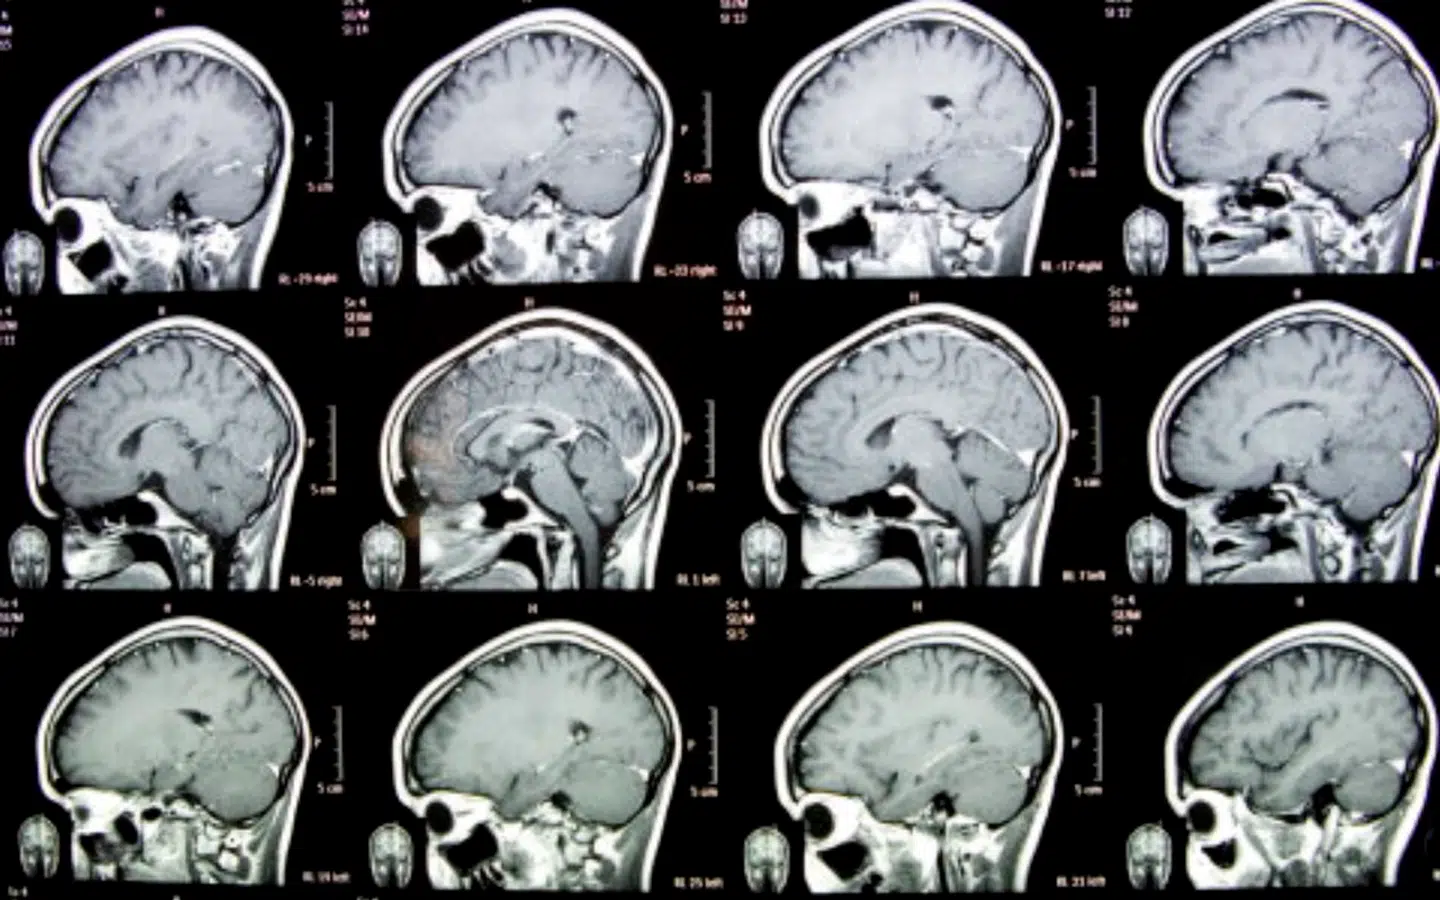

Professor i neurologi: Tre ting, der nedbringer risikoen for at blive ramt af en hjerneblødning

Hanne Christensen, der er klinisk professor i neurologi, måler sit blodtryk fire gange om året. Nu peger hun på, hvad du selv kan gøre for at nedbringe risikoen for at få en hjerneblødning, som det Søren Pape Poulsen blev ramt af.